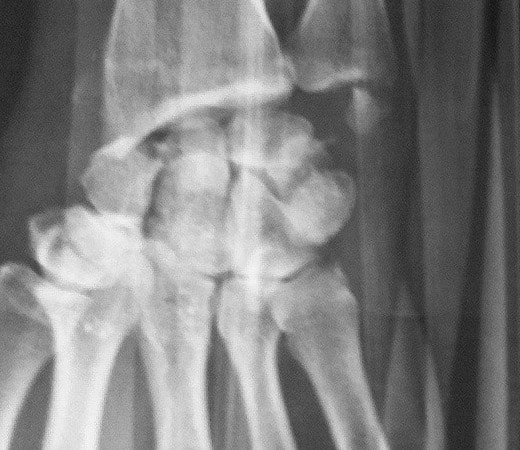

Le scaphoïde est un des os du carpe du poignet. Pièce maîtresse, véritable clef de voûte du poignet, il peut être le siège de fracture à la suite d’une chute sur la main. Cette fracture, peu douloureuse, passe parfois inaperçue ou est assimilée à une entorse et le patient ne consulte pas de spécialiste. Le diagnostic exige des clichés radiographiques à 15 jours d'intervalle, ou un scanner, qui permet plus sûrement de confirmer la fracture du scaphoïde.

Pseudarthrose du scaphoïde

Suite à une fracture du poignet, du fait de sa vascularisation particulière, si la fusion des pièces osseuses ne se fait pas, on parle de pseudarthrose du scaphoïde. Il s’agit d’une absence de consolidation des deux morceaux du scaphoïde Au-delà des délais habituels (6 mois), douleur et parfois gonflement du poignet invitent à un bilan radiographique, afin d’établir le diagnostic. Lorsqu’il est confirmé, un scanner et une IRM sont nécessaires afin d’établir le stade selon de l’affection et l’état de vascularisation de la partie haute du scaphoïde.